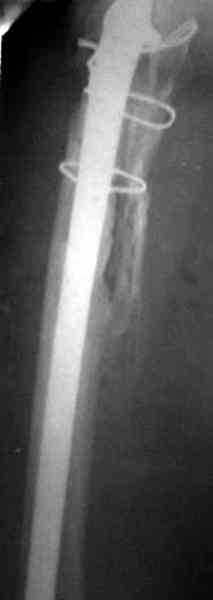

Наглухо ушитая рана с дренажом зажила первично, после чего с больной потерял контакт, и только недавно, через 8 лет я осмотрел её. Она без проблем нагружает на конечность и передвигается с помощью трости. От окончательной операции по реконструкции отказывается, довольная результатом.

Имеются литературные данные, когда спейсер держали не более 6 месяцев, но этот случай бьет все рекорды, может быть для наших людей, обременных финансовыми трудностями, нужна другая шкала оценки сроков нахождения спейсеров.

и последние снимки.